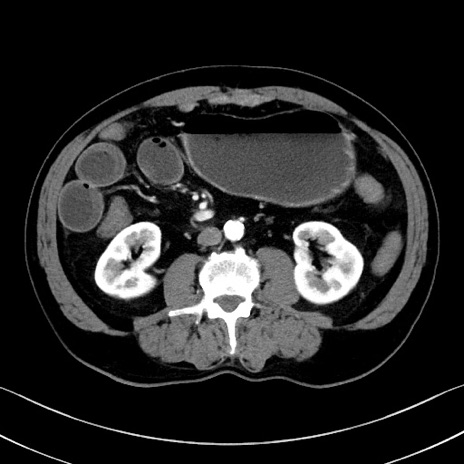

症例35(横断像)

【症例】70歳代 男性

【主訴】腹部膨満、嘔吐

【現病歴】昨日より腹部膨満感出現。本日増悪し、仙痛出現。嘔吐あり、受診。

【既往歴】糖尿病、胆摘後

【身体所見】BP 149/80mmHg、HR 74/min、BT 35.9℃、腹部:膨満、軟、圧痛なし。腸雑音減弱あり。上腹部正中切開瘢痕あり。

【データ】WBC 13500、CRP 1.72